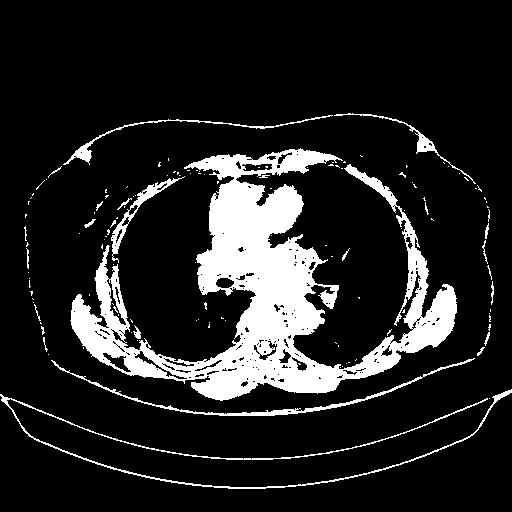

Original VENOUS CT scan

Full window (WL 1023.5, WW 4095 β†’ Low βˆ’1024, High +3071)

Actual HU range: [-1024.0, 3071.0]